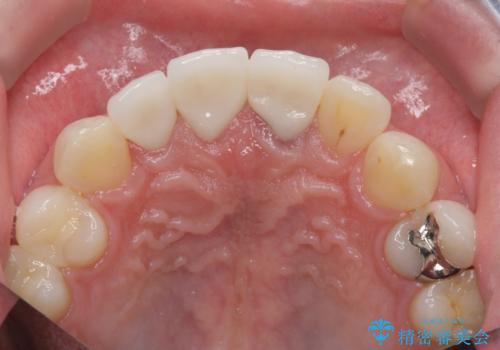

・歯の変色 →ジルコニアクラウンの製作

歯の挺出を行ったことで歯ぐきの腫れも改善され、安定した歯周環境下でのセラミッククラウン治療を行うことができました。